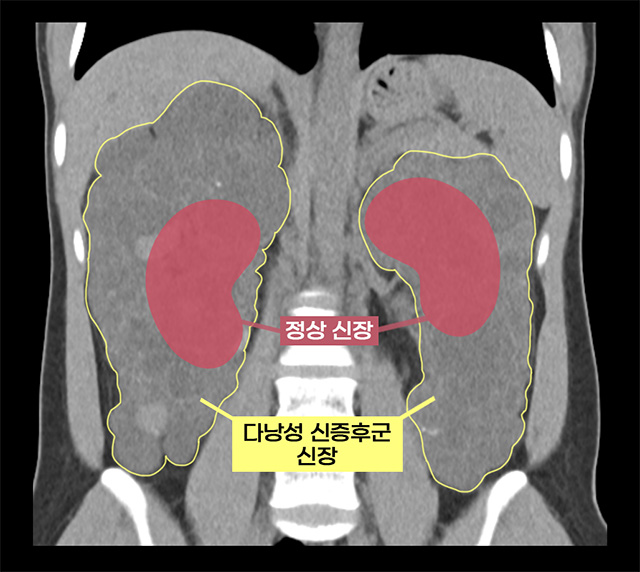

• 실제 다낭성 신증후군 환자의 신장과 정상 신장 비교 /이미지 제공=서울아산병원

▲ 실제 다낭성 신증후군 환자의 신장과 정상 신장 비교 /이미지 제공=서울아산병원

환자는 선천성 유전 질환인 상염색체 우성 다낭성 신증후군(ADPKD)을 앓고 있었다. 이 질환은 신장에 수백 개의 낭종이 생기며, 신장이 점차 커져 축구공 크기까지 커질 수 있고, 대부분 만성 신부전으로 이어진다. 감염, 출혈, 낭종 파열, 신장암 등의 합병증 위험이 높아 신장이식 시 기존 신장을 제거해야 하는 경우도 많다.